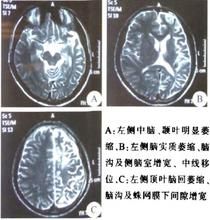

2.MRI

在疾病起始四個月內,大多數患者顯示一側半球的腦溝增寬,腦脊液腔隙增大,特別是在島葉或島葉周圍區域,伴隨皮層或皮層下高信號[T2或(和)FLAIR)],大多數病例的同側尾狀核頭萎縮,之後隨著病情的進展,病變側半球出現進行性的腦組織萎縮,腦室擴大,皮層或皮層下高信號範圍擴大。部分病例早期MRI掃描正常或顯示局灶性皮層腫脹,隨後受累的半球顯示廣泛的信號改變與萎縮。RE一般不出現MRI強化現象及MRA異常。部分套用激素治療的患者出現雙側半球的萎縮。PET和SPECT檢查亦能提未為一側半球性病變。